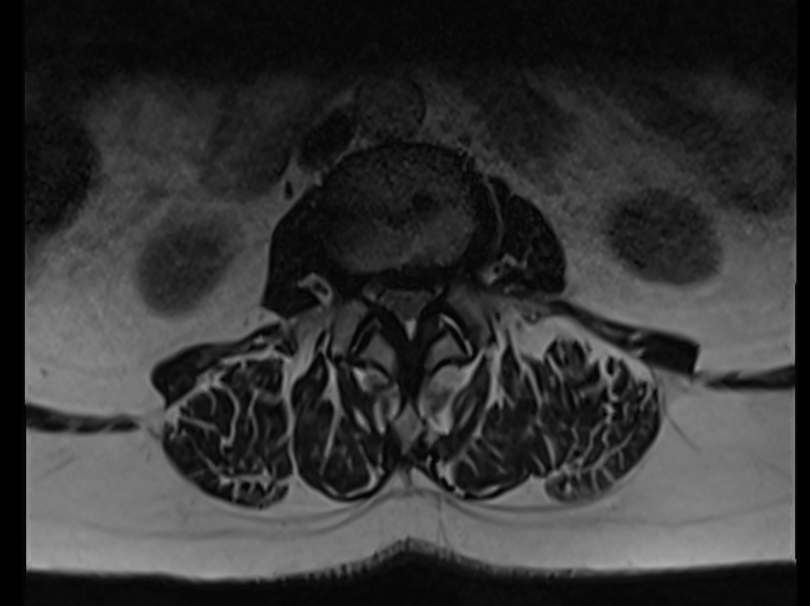

La colonne vertébrale est constituée de vertèbres au milieu desquelles passe le canal rachidien. Celui-ci contient, au sein d’une enveloppe que l’on appelle « sac dural », la moelle épinière et les racines nerveuses. Selon la constitution du patient ou lors d’usure naturelle (arthrose), un rétrécissement du canal rachidien peut survenir.

Canal Lombaire étroit